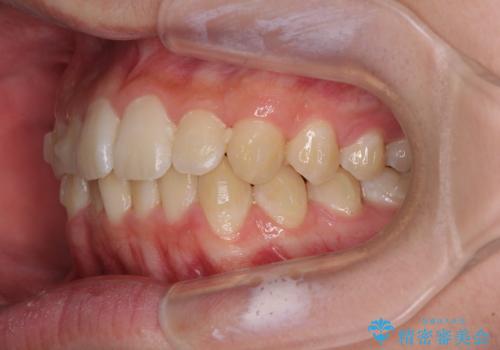

「しっかりと装着する」が実行でき、高校3年生の秋には治療を終えることができました。

入試時期に入ると、後戻り防止のリテーナー装着が疎かになる可能性があったり、リテーナーが壊れてしまった場合すぐに来院できなかったりというリスクがあったため、下顎前歯の舌側をワイヤーで固定することとしました。